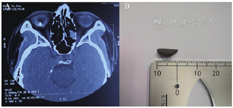

病例1:患者,男,46岁,以"右眼被铁渣击伤8 d"为主诉入院。2021年1月24日10时患者不慎被铁渣击伤右眼,即感眼球疼痛、视物不见,伴血性液体流出,当地医院急诊行"右眼球破裂伤修补术"7 d后转入我院。眼部检查:右眼视力光感,眼压7 mmHg(1 mmHg=0.133 kPa),球结膜混合充血,角膜10:00—6:00可见一斜形裂伤口,长约7 mm,缝线在位,颞上方及鼻下方周边前房深度1/2CT,余前房消失,瞳孔欠圆,虹膜后粘连,晶状体皮质溢出,向后窥不入;左眼未见异常。眼眶CT示:右眼球内异物(见图1A)。入院诊断:①右眼球内异物;②右眼外伤性白内障;③右眼创伤性脉络膜脱离。治疗:术中切除晶状体和玻璃体后,见全视网膜呈灰白色隆起,1、5、7点位不规则小裂孔形成,黄斑区上方视网膜变性,视盘下方视网膜可见一金属异物嵌顿,异物为铁质,大小10 mm×4 mm(见图1B),异物周围视网膜裂开,导光辅助眼内圈套器(见图2)将异物自视网膜上拔出,注入重水保护后极部视网膜,行角膜缘切口,圈套器将异物自角膜缘切口送出,间断缝合角膜缘切口,行裂孔处激光光凝,注入硅油5 ml,术后2个月复查视力为光感,术后半年复查视力为指数/1 m。

A:术前眼眶CT扫描图像;B:眼球内异物图片

A: Preoperative orbital CT scan. B: Picture of the intraocular foreign body.